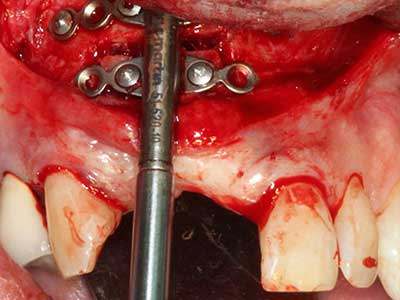

Indicazione: preparazione vicino ai nervi

Come descritto in precedenza, le indicazioni per la piezochirurgia si possono trovare anche nel campo della chirurgia odontoiatrica conservativa. Delle puntine particolari semplificano l'esposizione delle punte delle radici e facilitano la protezione dei nervi e delle membrane mucose del seno, in particolare nella regione dentale superiore e posteriore e in quella premolare inferiore. Le puntine angolate diamantate si utilizzano per preparare con precisione la cavità della resezione che ospiterà il materiale di riempimento della radice retrograda per l'otturazione apicale sigillata. Grazie alla tecnologia a ultrasuoni le puntine possono essere estremamente sottili, quindi la visibilità e le dimensioni di accesso della cavità sono migliori. Di conseguenza, l'applicazione della chirurgia a ultrasuoni per questa indicazione è una delle procedure standard per la resezione apicale (Del Fabbro, Tsesis et al. 2010, Scarano, Artese et al. 2012).

Indicazione: resezione apicale

Quando le procedure chirurgiche vengono eseguite sull'osso nelle immediate vicinanze di strutture sensibili, come vasi sanguigni o nervi, gli strumenti rotanti pongono un rischio significativo di lesione iatrogena. I dispositivi piezoelettrici possono essere utili per la preparazione delle coperture ossee e la rimozione del tessuto duro in prossimità dei nervi, in particolare per la loro esposizione dopo una lesione iatrogena, ma anche durante la lateralizzazione dei nervi per le procedure di resezione e ricostruzione o il posizionamento di impianti (figg. 17-20). Il contatto leggero tra puntina piezoelettrica e nervo non causa generalmente danni, ma se si procede senza prestare attenzione con movimenti a sega o raccordi con residui di substrati ossei possono verificarsi danni al nervo temporanei o anche permanenti. Il rischio di danno, tuttavia, è considerato sostanzialmente inferiore al rischio presente utilizzando seghe o frese (Pereira, Gealh et al. 2014).